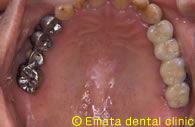

上顎の入れ歯があわない。自分の歯のように食べたい。

Before

After